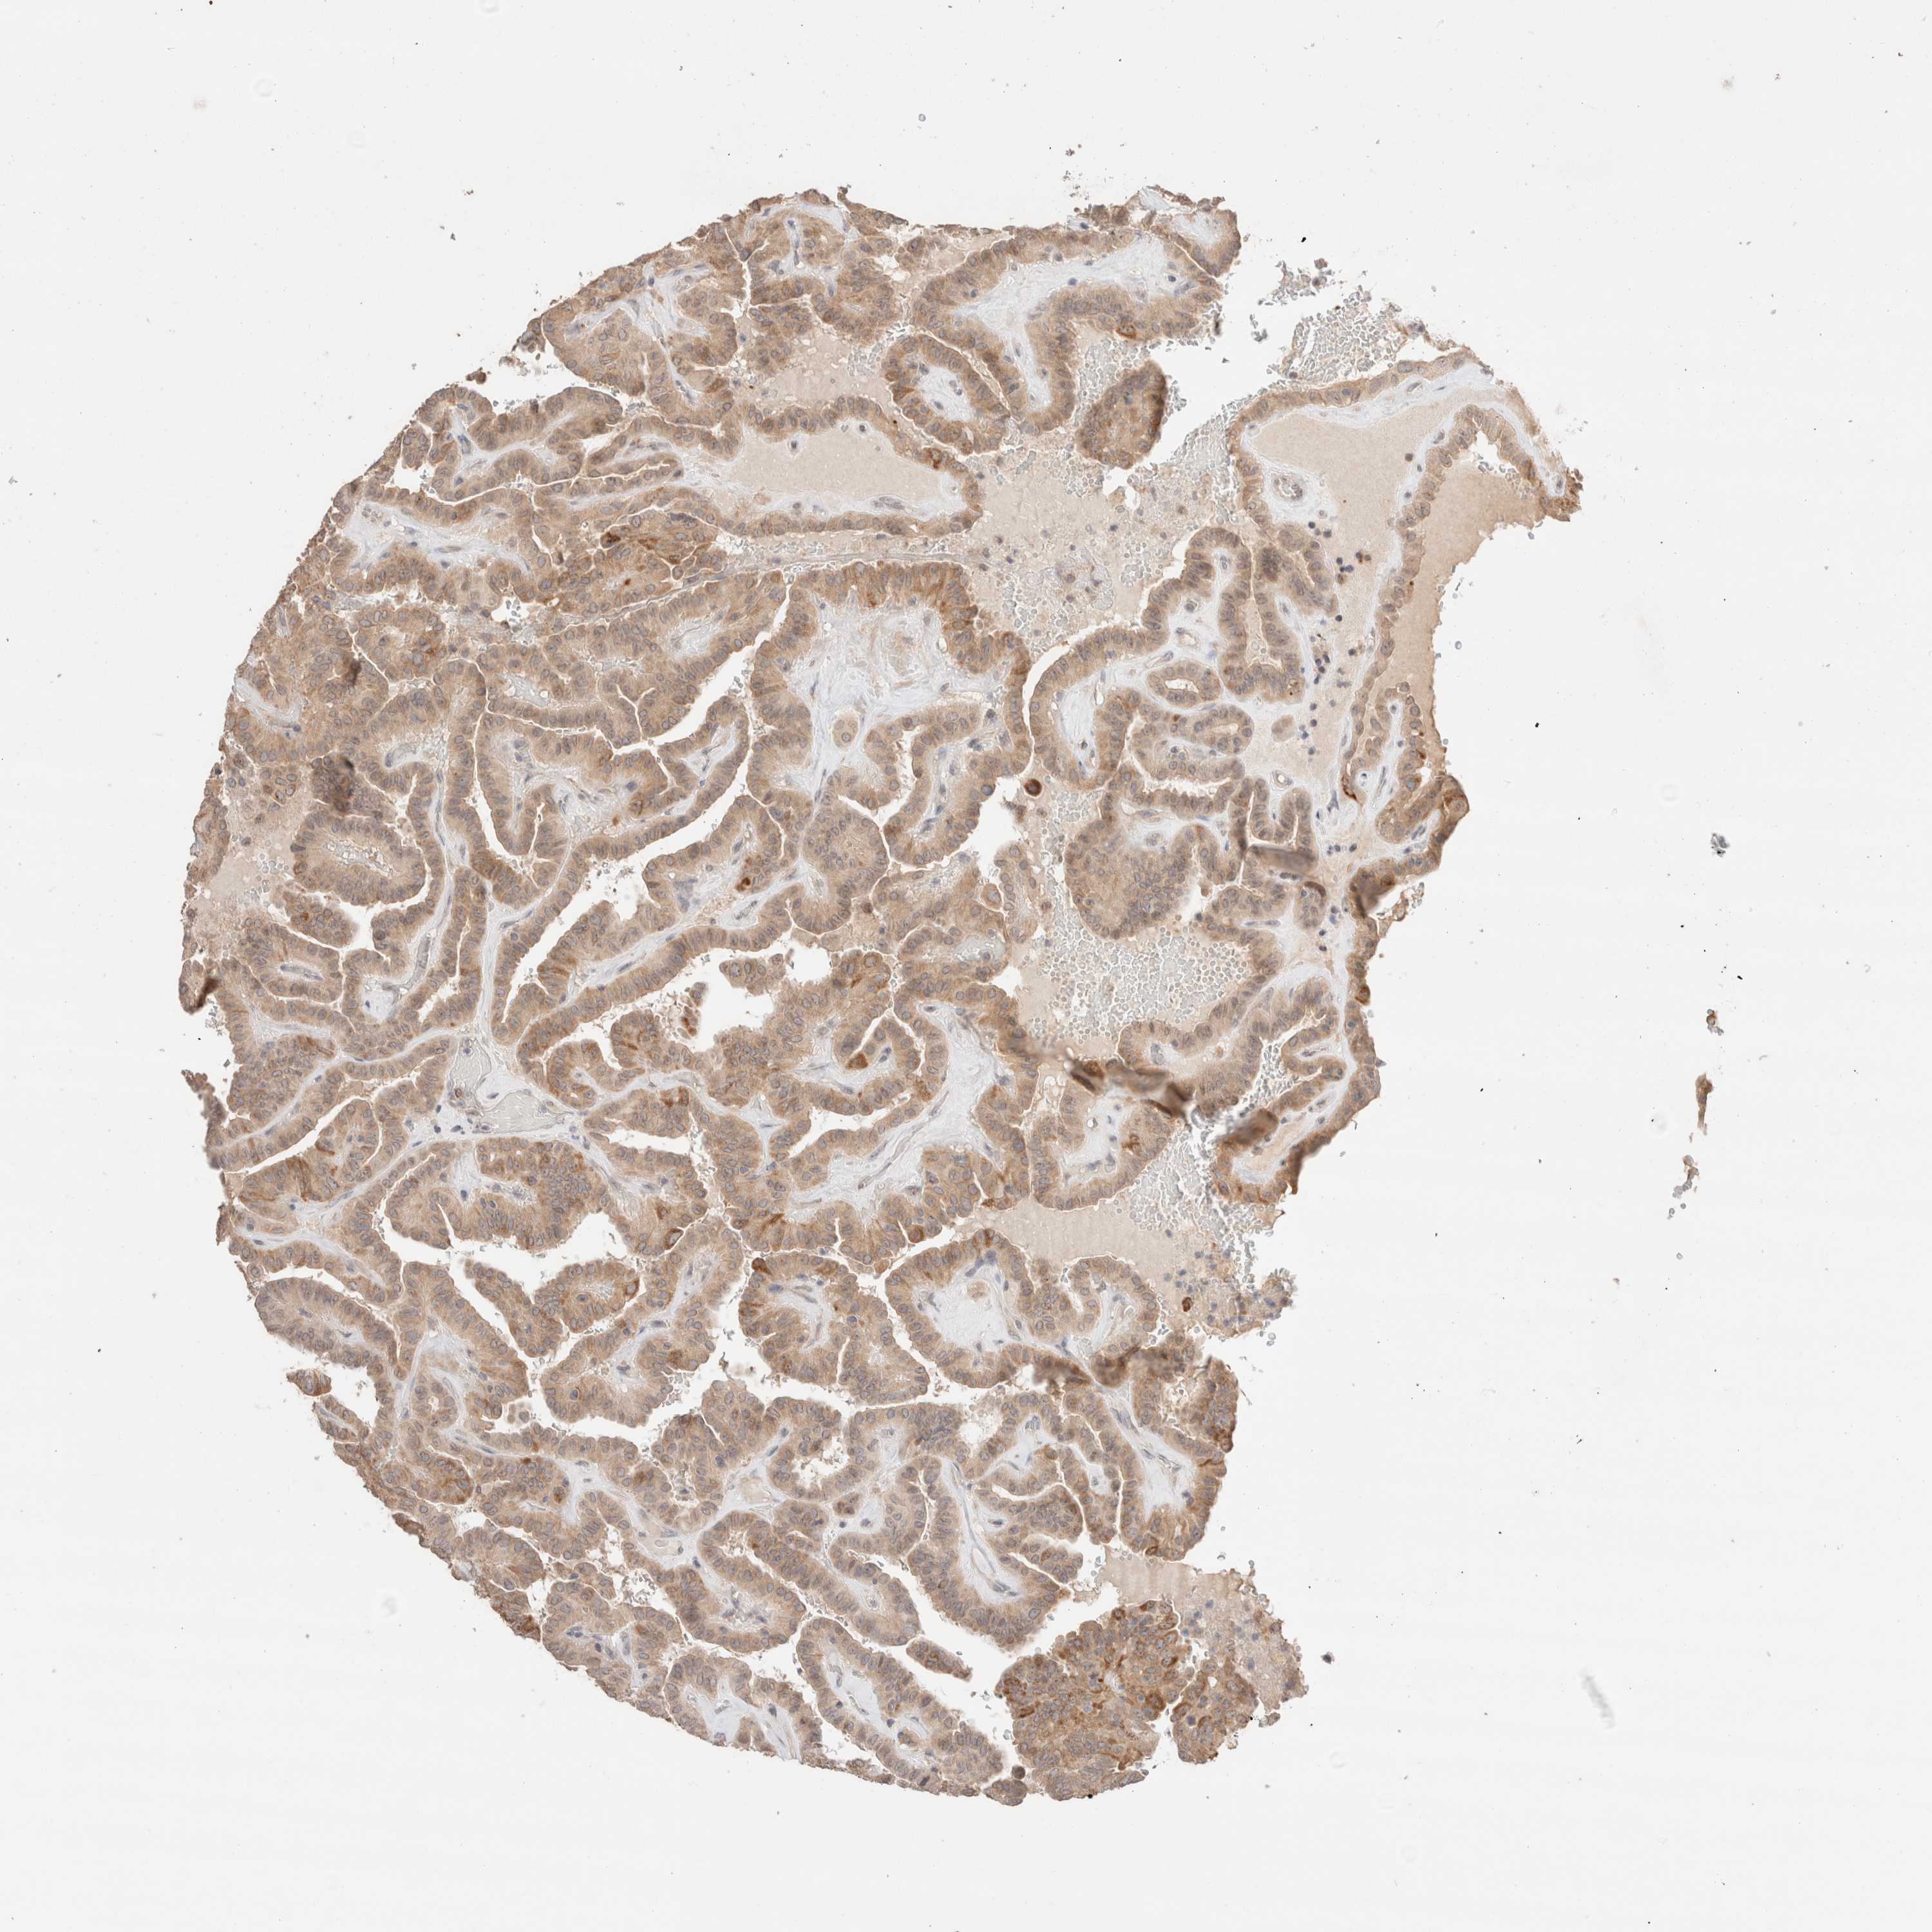

THYROID CANCER - Protein expressioni

A mouse-over function shows sample information and annotation data. Click on an image to view it in a full screen mode. Samples can be filtered based on level of antibody staining by selecting one or several of the following categories: high, medium, low and not detected. The assay and annotation is described here.

Note that samples used for immunohistochemistry by the Human Protein Atlas do not correspond to samples in the TCGA dataset.

Antibody stainingi

Antibody staining in the annotated cell types in the current human tissue is reported as not detected, low, medium, or high, based on conventional immunohistochemistry profiling in selected tissues. This score is based on the combination of the staining intensity and fraction of stained cells.

Each image is clickable and will lead to virtual microscopy that enables deeper exploration of all samples and also displays staining intensity scores, fraction scores and subcellular localization as well as patient and tissue information for each sample.

Antibody HPA024204

Staining

High

Medium

Low

Not detected

Intensity

Strong

Moderate

Weak

Negative

Quantity

>75%

75%-25%

<25%

None

Location

Nuclear

Cytoplasmic/membranous

Cytoplasmic/membranous,nuclear

Papillary adenocarcinoma, NOS

Follicular adenoma carcinoma, NOS